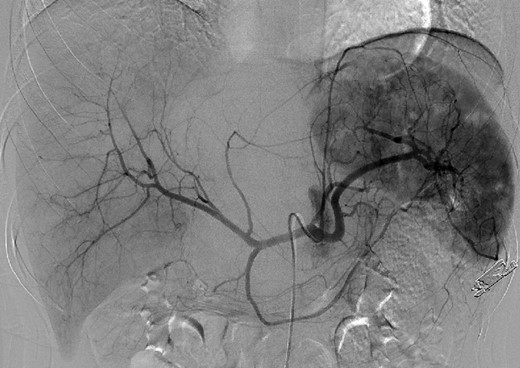

An 18-year-old woman presented with epigastric pain that started during a Japanese drum lesson. She was diagnosed with rupture of a hepatic tumor and transported to our hospital. She had no medical history of surgery, including abdominal surgery. Contrast-enhanced computed tomography (CT) revealed a 13-cm, low-density giant mass in the left hepatic lobe and high-density ascites, indicating abdominal bleeding from the liver tumor (Fig. 1). Ultrasonography confirmed a well-defined giant mass of the liver, comprising both cystic and solid lesions. Laboratory data showed a low hemoglobin level of 8.2 g/dl, and all the results of liver function tests and tumor marker measurement were within normal ranges. The patient underwent emergent celiac angiography, which revealed an avascular tumor with no evidence of extravasation from the hepatic artery. The left hepatic artery was considered to be the artery feeding the tumor and was embolized (Fig. 2). Magnetic resonance imaging (MRI) confirmed a well-defined giant multilocular lesion with fibrous partition (Fig. 3). After the patient's condition stabilized, she underwent left hepatic lobectomy. Laparotomy revealed bloody ascites and a large tumor in the left lobe of the liver; the right lobe appeared normal. The enlarged lymph nodes of the hepatoduodenal ligament were also dissected. Histological analysis of the resected specimen revealed a huge cystic mass of ∼12 × 9.5 cm. The mass was cystic and multilocular with a fibrous wall and filled with a massive blood clot (Fig. 4). The enlarged lymph node had a 25 × 23-mm cyst, which contained yellowish fluid. On microscopic examination, the wall of the cyst consisted of a tight elastic fiber meshwork composed of collagen fibers, which was accompanied by a small amount of acid mucopolysaccharide in the stroma and a lining of single-layered flat cells on the inner wall (Fig. 5a and b). Immunohistochemical staining revealed that the cyst wall was positive for both the endothelial marker CD31 and the lymphangial marker D2-40 (Fig. 5c and d). The cystic structure of the lymph node also was composed of elastic fiber components similar to those of the cyst in the liver and lined with single-layered flat cells, which were immunohistochemically positive both for CD31 and D2-40 (Fig. 5e). The pathological diagnosis was hepatic lymphangioma combined with lymphangioma of the lymph nodes. The patient's postoperative course was uneventful, and she was discharged on Day 8. During follow-up for almost 4 years since the surgical treatment, the patient has presented no sign of recurrence.

MRI confirmed a well-defined giant multilocular lesion with fibrous partitioning.